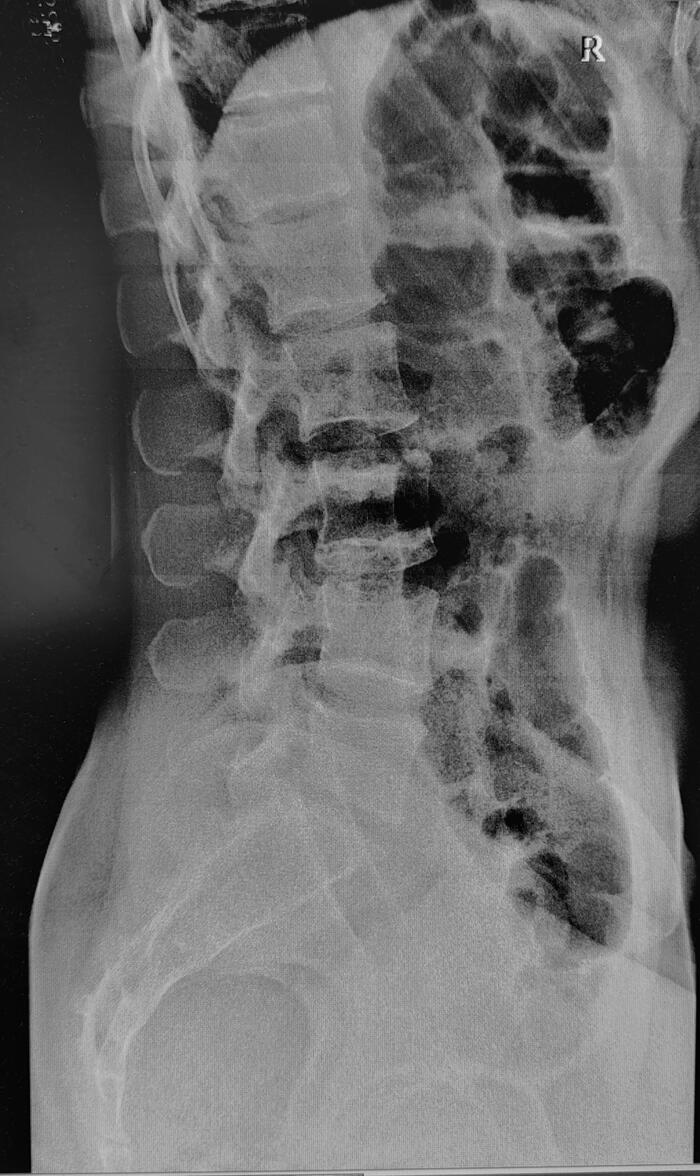

Рентгенограммы поясничного отдела позвоночника пациента с длительным, выраженным болевым синдромом(6 мес.) в пояснице, с временным эффектом от приема НПВС. При описании снимков выраженной костной патологии в поясничном отделе позвоночника не выявлено: структура тел позвонков не изменена, травматических, деструктивных изменений не выявлено, субхондральный склероз замыкательных пластин тел позвонков отсутствует, краевые остеофиты тел позвонков не выявлены, имеется не выраженное неравномерное сужение межпозвонковых щелей как начальное проявления остеохондроза-такая рентгенологическая картина не дает столь выраженного и длительного болевого синдрома.

Обращают на себя внимание крестцово-подвздошные сочленения(КПС),отмечается неравномерное не выраженное сужение щелей КПС с локальными участками расширения, субхондральный склероз- более выраженный слева, имеются двусторонние краевые остеофиты, в нижней трети левого КПС суставная щель не ровная, "изъеденная", по причине наличия единичных эрозий костной ткани. Заключение: Двусторонний сакроилиит 2 ст.(более выраженный слева).

В дальнейшем пациенту потребуется стац. обследование в ревматологическом отделении т.к. наиболее часто сакроилиит является проявлением анкилозирующего спондилита(болезнь Бехтерева), потребуются такие обследования: